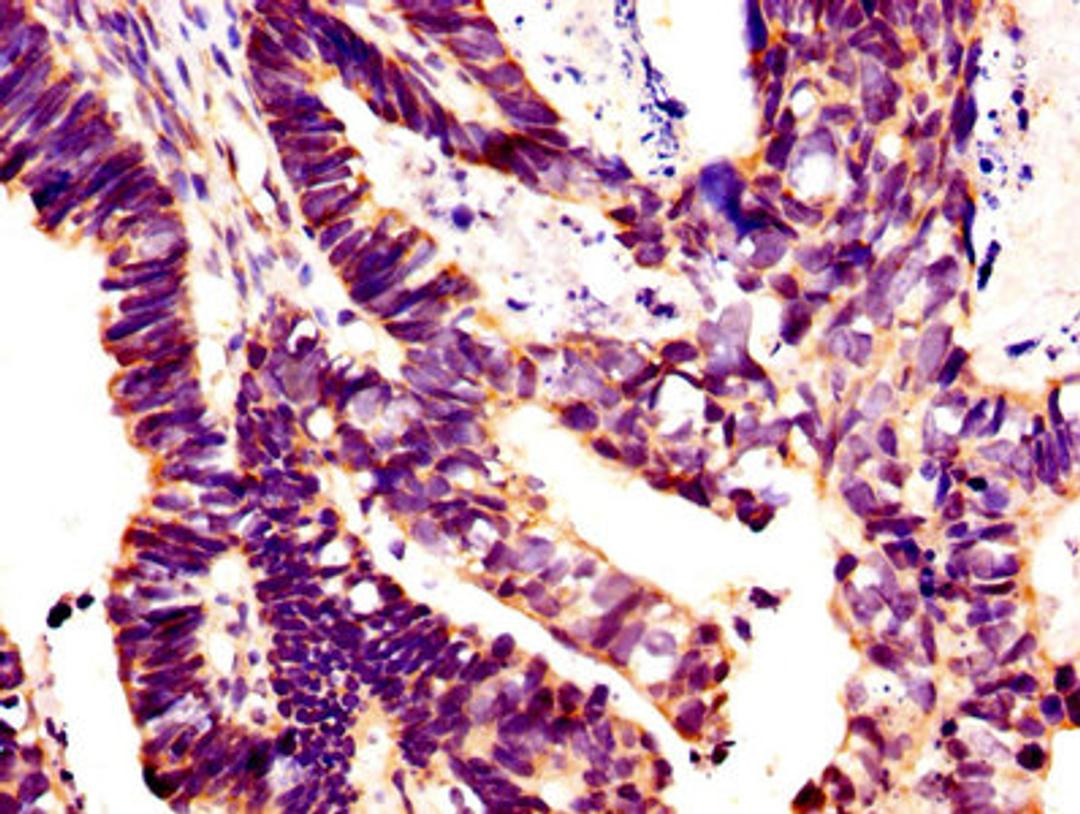

IHC image of CSB-PA12989A0Rb diluted at 1:400 and staining in paraffin-embedded human ovarian cancer performed on a Leica BondTM system. After dewaxing and hydration, antigen retrieval was mediated by high pressure in a citrate buffer (pH 6.0). Section was blocked with 10% normal goat serum 30min at RT. Then primary antibody (1% BSA) was incubated at 4°C overnight. The primary is detected by a biotinylated secondary antibody and visualized using an HRP conjugated SP system.